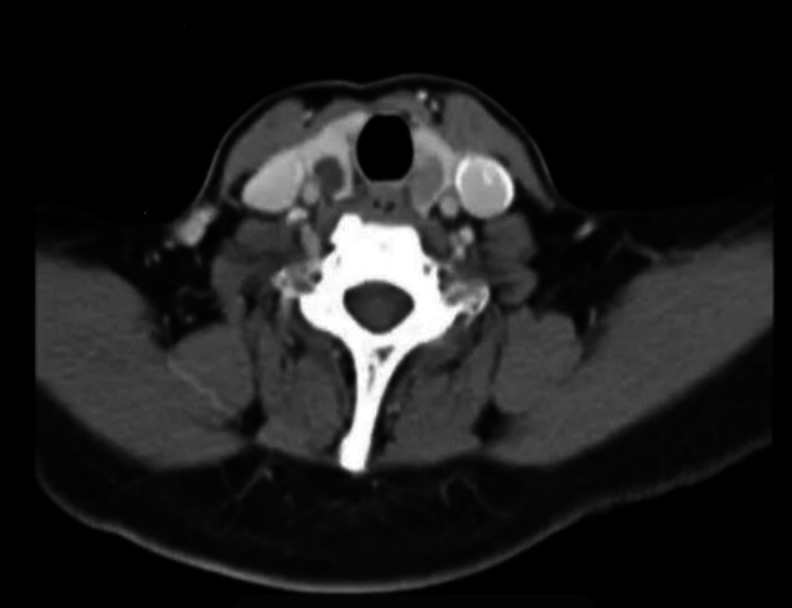

Case reports: We describe a novel case where primary papillary thyroid carcinoma (PTC) was found after a trans-oral excision of a tumor containing ectopic thyroid tissue at the posterior pharynx, an area not known to be a location for ectopic thyroid. Delays due to the COVID-19 pandemic resulted in regional cervical metastases and multifocal PTC. The female patient successfully underwent total thyroidectomy, selective cervical and central lymph node dissection, followed by adjuvant radioactive iodine ablation, with no evidence of distant metastases.